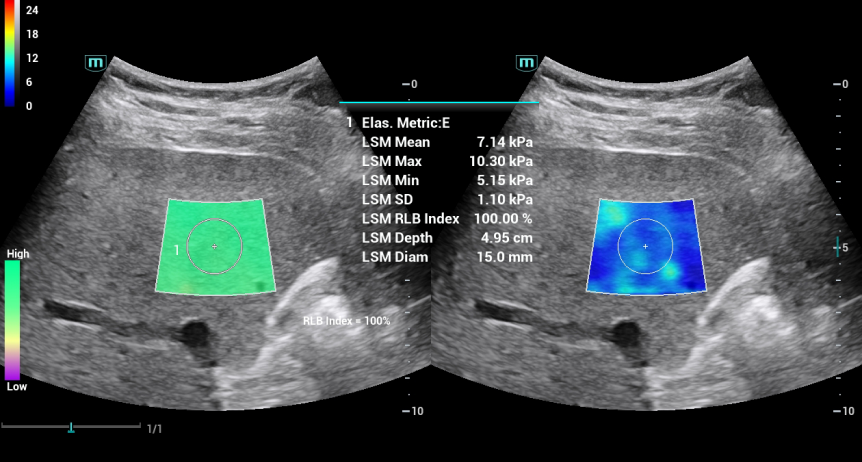

ELASTOGRAFIA SHARE WAVE